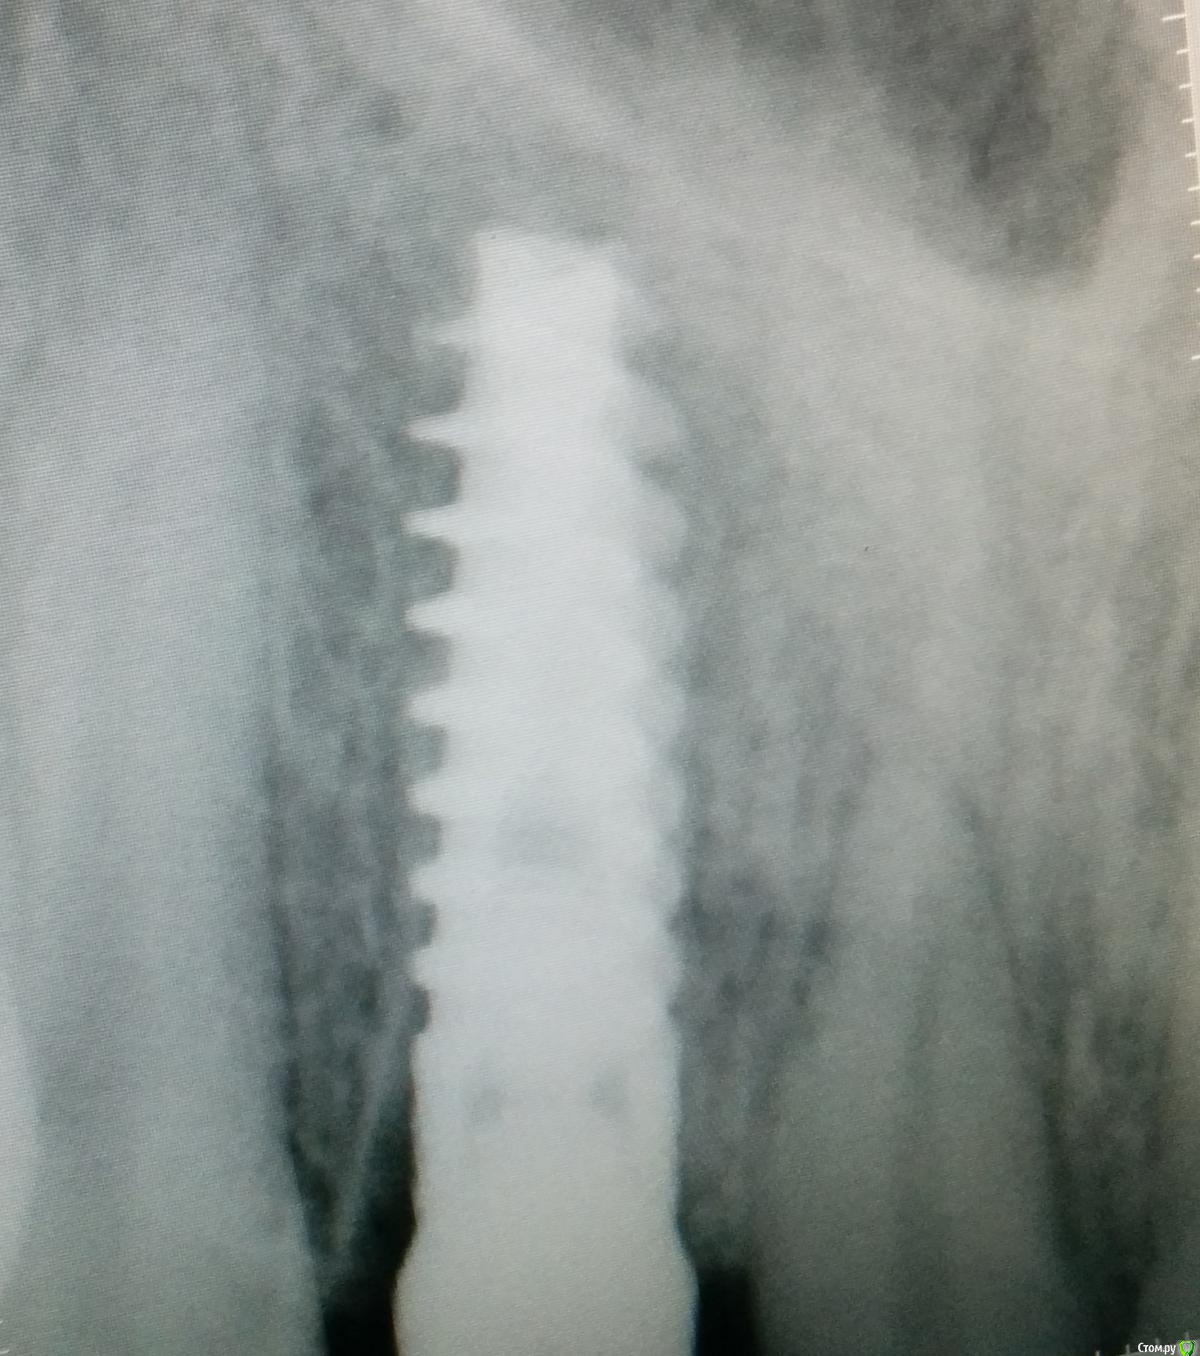

an_ver Опубликовано 2 апреля, 2015 Поделиться Опубликовано 2 апреля, 2015 SPI? В лунку что нибудь кидали во время установки? Ссылка на комментарий

MenshikovDV Опубликовано 2 апреля, 2015 Автор Поделиться Опубликовано 2 апреля, 2015 Нет, ничего не кидали. Ссылка на комментарий

Lolopop Опубликовано 3 апреля, 2015 Поделиться Опубликовано 3 апреля, 2015 альфабио?)))какой торк получили? Ссылка на комментарий

АнтонТЛТ Опубликовано 4 апреля, 2015 Поделиться Опубликовано 4 апреля, 2015 Судя по фото Alpha bio SPI, торк около 40 Ссылка на комментарий

MenshikovDV Опубликовано 5 апреля, 2015 Автор Поделиться Опубликовано 5 апреля, 2015 торк намного больше 40 Ссылка на комментарий

Brigita Опубликовано 5 апреля, 2015 Поделиться Опубликовано 5 апреля, 2015 на удаленном зубе какая то железячка хвостиком торчит))) Ссылка на комментарий

Saymon Опубликовано 6 апреля, 2015 Поделиться Опубликовано 6 апреля, 2015 на удаленном зубе какая то железячка хвостиком торчит)))Все нормально. Это WI-FI антенна. 4 Ссылка на комментарий

MenshikovDV Опубликовано 7 апреля, 2015 Автор Поделиться Опубликовано 7 апреля, 2015 ИНСТРУМЕНТ сломан в канале )) Ссылка на комментарий